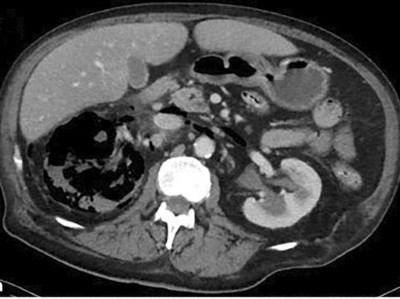

Gas, E. coli, Diabetes – in diesem Notfall sind Sie gefragt

Ein unkontrollierter Diabetes mellitus besteht bei bis zu 95 % der Patienten mit emphysematöse Pyelonephritis. So auch bei dem 55-jährigen Patienten, der notärztlich mit dem Leitbild eines akuten Abdomens vorgestellt wird. Die Diagnose ist nur radiologisch möglich. Ursächlicher Erreger in diesem Fall ist E. coli. Wissen Sie, wie therapiert wird?

Arzt reicht Patientin Urinbecher/© terovesalainen / stock.adobe.com (Symbolbild mit Fotomodellen), Urintest/© AlexRaths / Getty Images / iStock, Person hält sich den Bauch/© anut21ng Stock / stock.adobe.com (Symbolbild mit Fotomodell), Laborkraft benetzt einen Urinteststreifen/© Lothar Drechsel / Stock.adobe.com (Symbolbild mit Fotomodell), Injektion in einen venösen Zugang/© sudok1 / Getty Images / iStock, Arzt tastet Bauch eines Mannes ab/© Kate / Stock.adobe.com (Symbolbild mit Fotomodell), Senior hält Tabletten und Glas Wasser in den Händen/© Andrii Zastrozhnov / Stock.adobe.com (Symbolbild mit Fotomodell), Teststreifen zur Urin-Analyse/© Chamaiporn / stock.adobe.com, Junge Frau erhält Infusion im Krankenhaus/© Pitchayaarch / stock.adobe.com (Symbolbild mit Fotomodell), Spritze wird aufgezogen/© scyther5 / Getty Images / iStock, Junge Frau sitz auf dem Bett und hält sich den Bauch/© Siarhei Khaletski / Getty Images / iStock (Symbolbild mit Fotomodell), Springer Medizin Podcast - Antibiotikatherapie/© Viewfinder / stock.adobe.com, Sonographien Ureteropelviner Stenosen/© Dr. Kammer / LMU München (mit freundlicher Genehmigung), Impfbuch und Spritze/© Henrik Dolle / stock.adobe.com, Drei Blutteströhrchen für sexuell übertragbare Infektionen/© Sherry Young / stock.adobe.com (Symbolbild), In-Vitro Fertilisation/© Christoph Burgstedt / stock.adobe.com, Epididymitis mit verdicktem Nebenhodenkopf, entzündlicher Hyperämie und Begleithydrozele/© Rosellen J et al. / all rights reserved Springer Medizin Verlag GmbH, Jugendlicher im Gespräch mit Ärztin/© JackF / Getty Images / iStock (Symbolbild mit Fotomodellen), Impfung/© DragonImages / stock.adobe.com, Junge Patientin im Gespräch mit einer Ärztin/© FatCamera / Getty Images / iStock (Symbolbild mit Fotomodellen), Klebsiella-Balanitis am Penis/© 2024 European Academy of Dermatology and Venereology, Lila-gefärbter Urin in einem Katheterbeutel/© Franzoi M et al. / all rights reserved Springer Medizin Verlag GmbH, Emphysematöse Pyelonephritis in der kontrastmittelgestützten CT/© Taskin B et al. / all rights reserved Springer Medizin Verlag GmbH, Point of Care Test auf HIV/© Sodel Vladyslav / stock.adobe.com (Symbolbild mit Fotomodellen), Medikamente werden aus dem Schrank geholt/© I Viewfinder / stock.adobe.com (Symbolbild mit Fotomodell), Titelbild Kongress Kompakt EADV 2024/© Hintergrundbild: gnoparus / stock.adobe.com, Search Icon, Älterer Mann mit Tabletten in der Hand/© vorDa / Getty Images / iStock (Symbolbild mit Fotomodell), Mann erleidet Schwindel/© Tunatura / Getty Images / iStock (Symbolbild mit Fotomodell), Stereotaktische Strahlentherapie (SBRT) einer solitären ossären Metastase in dem Brustwirbelkörper/© Springer Medizin Verlag GmbH, Einem Mann wird Blut abgenommen/© auremar / stock.adobe.com (Symbolbild mit Fotomodellen)